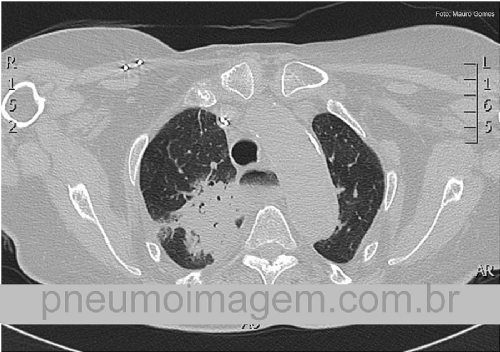

CASO CLÍNICO #9Paciente do sexo feminino, 87 anos, apresenta tosse crônica, síndrome consumptiva e queda do estado geral. Nega febre e dispneia. Qual a sua hipótese diagnóstica? Deixe os seus comentários abaixo!

Female patient, 87 years old, has chronic cough, wasting syndrome, and poor general condition. Denies fever and dyspnea. What is your diagnosis? Leave your comments below!

Acalásia do esôfago com pneumonia por broncoaspiração